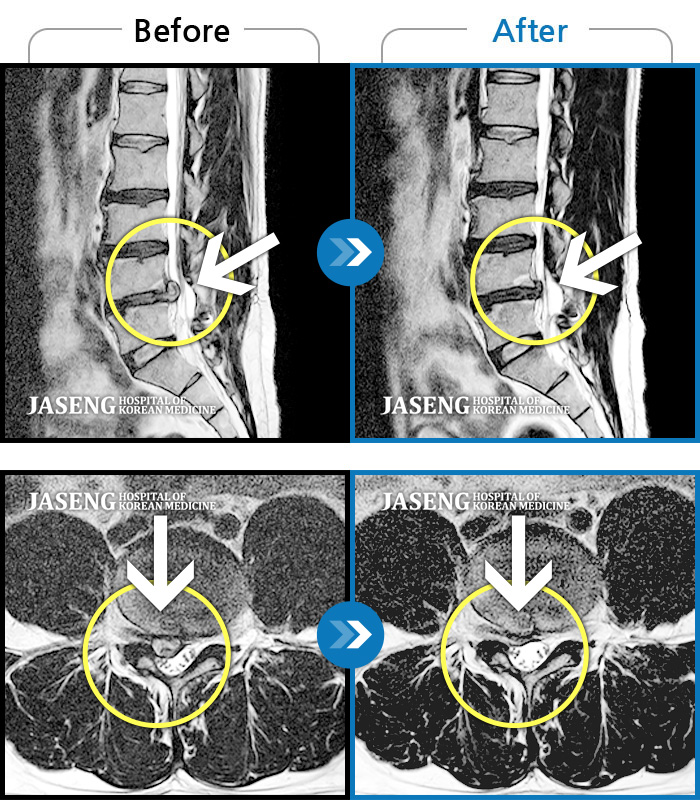

허리디스크

천안 · 윤영웅 원장

허리와 좌측 다리 통증, 저림이 심해요.

촬영시기

2021.10.25 ~ 2022.05.21

2022.05.24